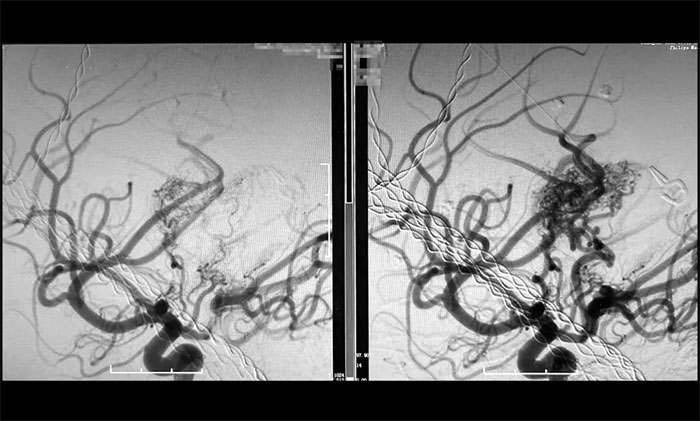

近期,盧云鶴博士團(tuán)隊(duì)成功完成一例高難度巨大腦動靜脈畸形栓塞術(shù)。該病例為兒童腦深部核心功能區(qū)高危復(fù)發(fā)型AVM,血流動力學(xué)復(fù)雜(伴盜血和靜脈球),且已多次出血,患兒危在旦夕。如果不治療,必然再次出血,下一次可能就是災(zāi)難性的。再次手術(shù)治療,就如同走鋼絲,面臨著術(shù)中即刻的大出血和腦梗死兩大致命/致殘風(fēng)險(xiǎn)。最終,盧云鶴博士團(tuán)隊(duì)迎難而上,在多支穿支動脈供血并合并假性動脈瘤的極端條件下,借助術(shù)中功能監(jiān)測(電生理+mini-wada試驗(yàn))輔助下,成功實(shí)施超選擇性介入栓塞,最終實(shí)現(xiàn)畸形團(tuán)完全栓塞,且未造成神經(jīng)功能損傷。

▲ 巨大腦動靜脈畸形(右)被順利栓塞(左)